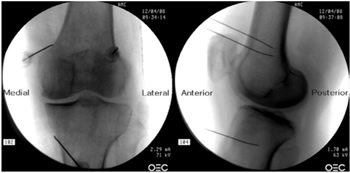

25. El-Hakeim EH, Elawamy A, Kamel EZ, Goma SH, Gamal RM, Ghandour AM, et al. Fluoroscopic guided radiofrequency of genicular nerves for pain alleviation in chronic knee osteoarthritis: A single-blind randomized controlled trial. Pain Physician. 2018;21(2):169-77.